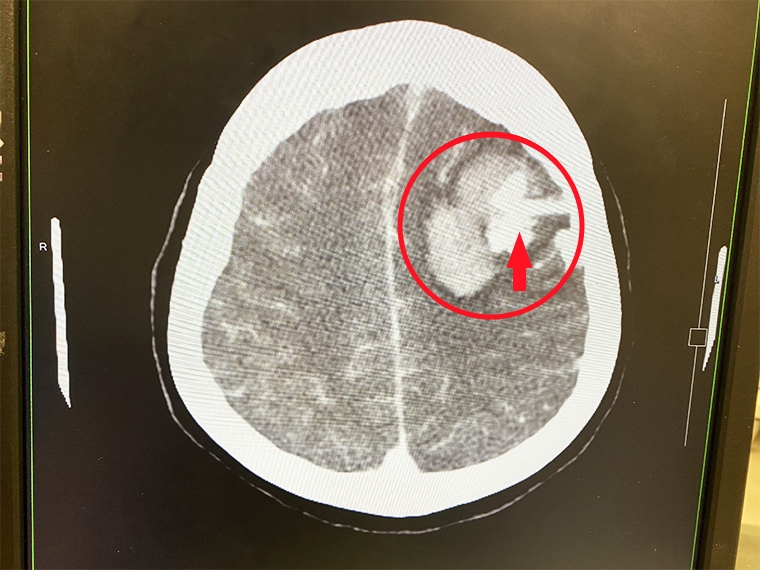

▲官女士電腦斷層檢查結果顯示,紅圈處為腦出血、箭頭處為動靜脈畸形。(圖/長安醫院提供)

【NOW健康 陳郁茹/台中報導】55歲官女士晚間突然昏迷,家人趕緊將她送至急診,初步檢查,發現頭部左側有大片腦出血。由於病患平常健康且無三高等不良習慣,醫師認為病灶不尋常,遂安排注射顯影劑的電腦斷層掃描,才發現患者是大腦動靜脈畸形出血。經緊急手術後,成功清除了血塊和異常的血管,官女士也恢復意識清醒,後續安排復健治療。

長安醫院神經外科醫師朱彥澤安排病人進行電腦斷層檢查確診,官女士患有腦出血合併動靜脈畸形。由於出血太大片了,時間拖越久對腦部造成永久性傷害的機率越高,情況相當危及,若不及時處理,病情可能會惡化至變成植物人的地步。